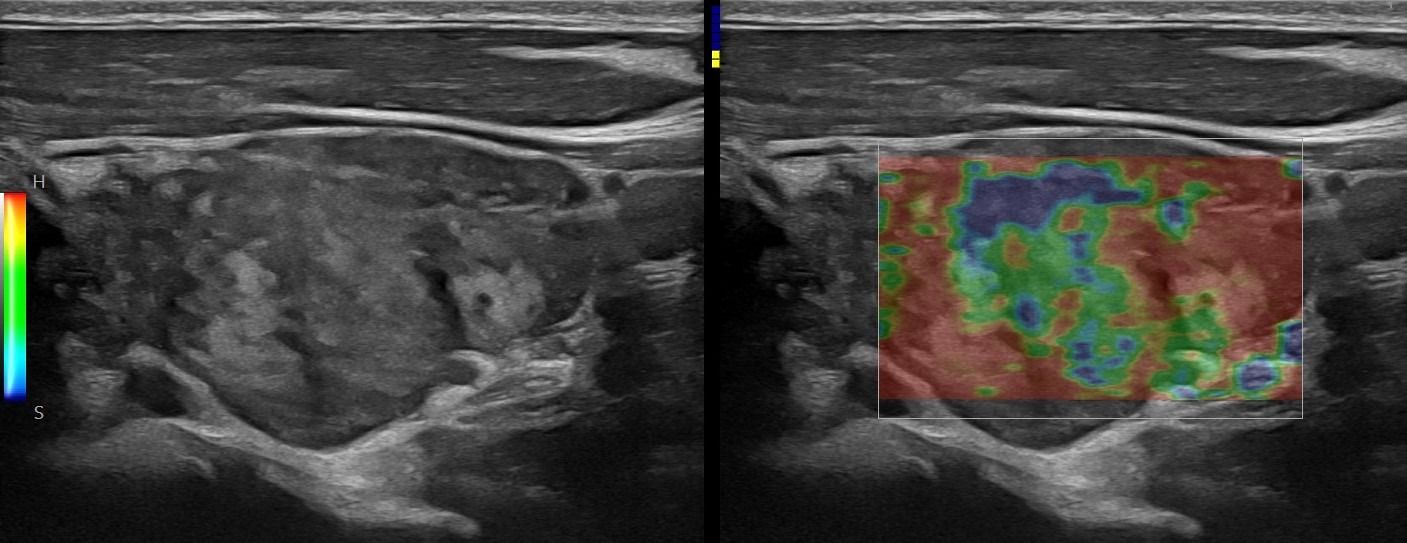

Με την τριπλή μελέτη του Θυρεοειδούς Αδένα, που περιλαμβάνει το B-Μode, το Έγχρωμο Υπερηχογράφημα και την Ελαστογραφία, γίνεται μια ολοκληρωμένη χαρτογράφηση του θυρεοειδούς αδένα. Το περίγραμμα, η αγγείωση και η ελαστικότητα του αδένα, καθώς και η υφή μίας πιθανής βλάβης αξιολογούνται με ακρίβεια και αξιοπιστία.